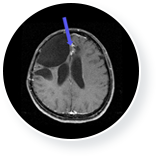

• 뇌종양 치료 후  이미지

뇌종양 치료 후